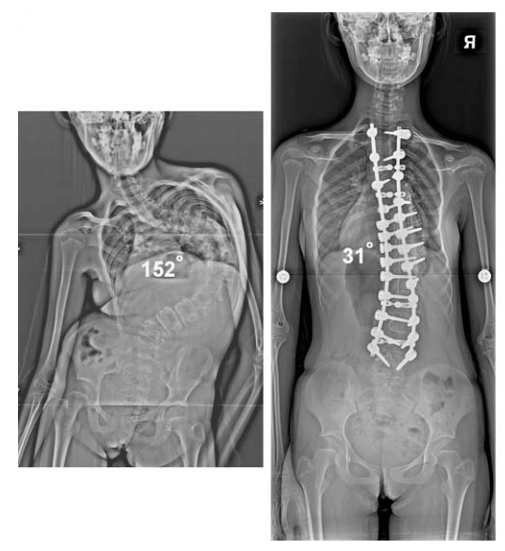

¤â³NÁB¥¿¹ê¨Ò¡G·¥ÄY«°¼Ås·î§Î¥H¤Ó·¥´Õ¤}®Ú°v´Ó¤Jªk¥iºë·Çªº´Ó¤J¨C¤@®Ú´Õ¤}®Ú°v¡A¥H´£¨ÑéT¤§°ò¼Î¡A¤Î±j¤jªºÁB¥¿¤O¥H¹F¦¨²z·QªºÁB¥¿¡C